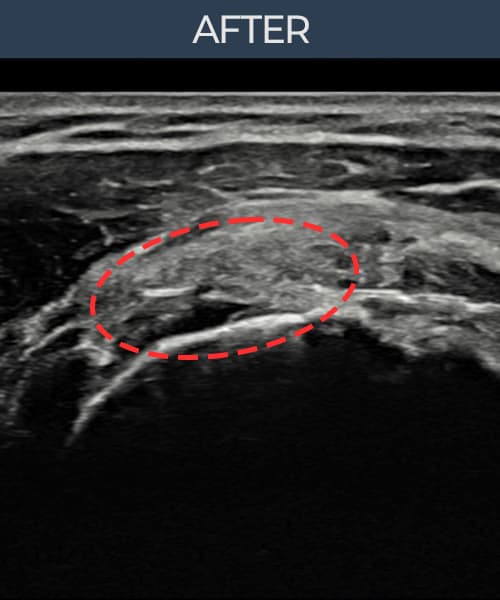

[촬영시기:21.09.02~21.10.07]

[석회분쇄흡입술] 좌측 어깨 통증으로 팔을 옆으로 올리기 어려워진 60대 남성 환자로, X-ray에서 좌측 극상근건 내 석회 침착이 확인되어 석회분쇄흡입술을 시행하였습니다.